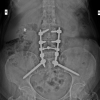

These investigations pointed diagnosis toward ART-induced Fanconi syndrome [3] and pathological fractures. The patient had pain in both upper limbs initially. One week later, she developed hip pain. Upper limb fractures occurred first, followed by a right subtrochanteric femur fracture. We started her on oral calcium and Vitamin D supplementation. In ART Regimen, tenofovir was stopped and Zidovudine added after consulting infectious disease department. Right sided subtrochanteric femur fracture operated with proximal femur nail and right upper limb fractures with titanium elastic nail.

Left-sided ulna shaft fracture conservatively managed with closed reduction and cast. Left lower limb fracture is also managed conservatively. The patient was followed up with serial X-rays and blood investigations at 3, 6, 9, and 12 months and assessed with Harris Hip Score (HHS) [4] and Upper Extremity Functional Index (UEFI) [5]. The patient was started on full weight-bearing walking at 6-week post-surgery. At 3-month post–surgery, functional assessment of both upper limb and lower limbs showed the patient having slight difficulty in household activities and mobilization was limited within the home. Blood parameters were also showed normal values by the end of 3 months. Follow-up blood investigation showed satisfactory levels of CD4 cells count. At 9-month postoperative, the patient had slight occasional pain in the right hip but walked without limp and support.

Currently, she uses public transport and is able to squat and sit crossed legged without any difficulty. She is able to walk and climb stairs without any discomfort. Active flexion of right hip is 0–120°, abduction of 0–40, adduction of 0–40, internal rotation of 0–30, and external rotation of 0–40° at 12-month post-surgery. Implant removal is planned once bone quality is improved. Lower limb implant is planned to remove only if the patient has pain or implant loosening.